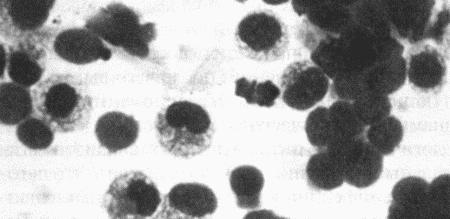

Вагинальная цитология

Повышение концентрации эстрадиола в период проэструса стимулирует деление клеток в базальных слоях вагинального эпителия, но затем концентрация эстрадиола, а соответственно и эндокринная поддержка образования нового, многослойного эпителия снижается, поэтому в образце обнаруживается больше мертвых ороговевших клеток. По мере развития проэструса снижается количество эпителиальных клеток, содержащих ядро. С начала до середины проэструса в вагинальных мазках обнаруживают повышенное содержание эритроцитов. Пик ороговения совпадает с началом повышения концентрации прогестерона; однако в начале эструса исследование не обнаруживает характерных особенностей, которые могли бы указывать на начало фертильного периода. Как правило, такой период наступает несколькими днями позже (табл. 1.1). Тем не менее вагинальная цитология остается популярным методом определения репродуктивного статуса суки из-за своей дешевизны, простоты и доступности. Для получения образца используют ватный тампон, предпочтительно небольшой, который вводят во влагалище и осторожно берут мазок. Полученные клетки помещают под микроскоп, а затем окрашивают контрастным (трихромом) или неконтрастным (например, препаратом Diff-Quik) веществом. При таком окрашивании мертвые кератинизированные клетки становятся оранжевыми, тогда как активные ядерные клетки, а также базальные и парабазальные эпителиальные клетки приобретают различные оттенки от голубого до зеленого.

Ближе к окончанию эструса вагинальные выделения претерпевают характерные изменения (снова выявляются эпителиальные клетки, содержащие ядро, и появляется большое количество лейкоцитов). Такая картина обычно наблюдается через 7–9 дней после пика ЛГ и известна как «вагинальный мазок метэструса». Изменению характера выделений предшествует переходный период, характеризующийся возрастающим количеством активных клеток и указывающий на окончание фертильного периода и эструса (табл. 1.1).

Вагинальная цитология весьма информативна в плане определения фазы эстрального цикла, однако значительные расхождения во времени появления основных признаков эструса по отношению к пику фертильности ограничивает применение указанной методики.

Фиг. 2.2.

Вагинальные выделения кошки (а). Выделения, типичные для фазы эструса. Большая часть клеток представляет собой безъядерные кератинизированные клетки или клетки с пикнотическим ядром. Присутствуют промежуточные клетки (b). Выделения, характерные для метэструса, — «течки», иногда наблюдаемой у кошек в конце эструса. Присутствуют поверхностные и промежуточные клетки, повышено содержание лейкоцитов. Этот короткий метэструс наблюдается в течение 24–48 часов (см. Приложение)